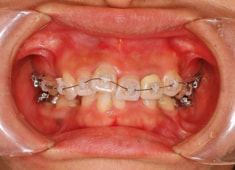

治療開始時